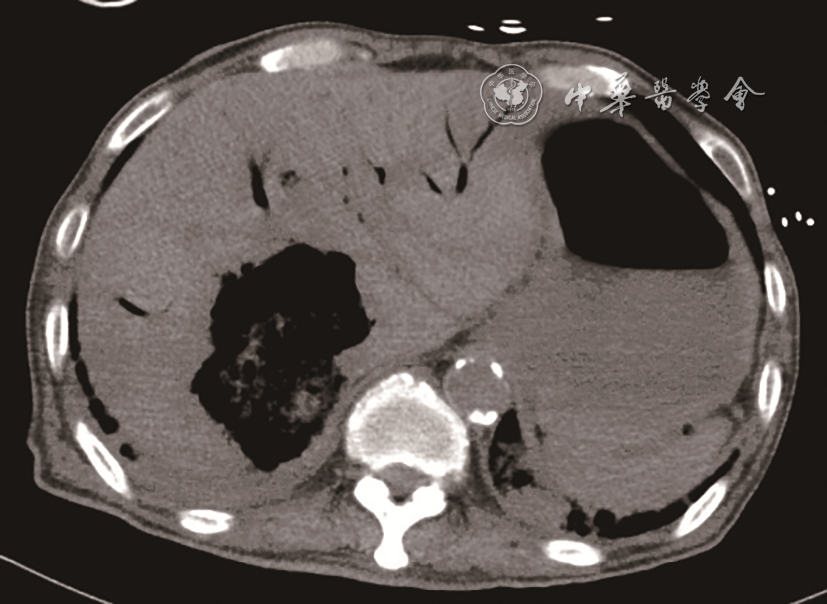

入急诊科时患者血压为60/29 mmHg(1 mmHg=0.133 kPa),心率为143次/min,末梢氧饱和度低,气管插管呼吸机辅助通气。11月26日急诊床旁超声检查提示:肝内多发高回声包块并肝静脉内气体样强回声漂动入下腔静脉、右心,肺动脉内可见大量气体样强回声,考虑产气型肝脓肿破裂(图12动态图1)。急诊平扫CT检查提示:肝多发类圆形混杂气体密度灶,肝内外胆管扩张、积气(图3)。当日血培养检出高黏性肺炎克雷伯菌(Klebsiella pneumoniae,KP),菌拉丝阳性,毒理强。血常规检查结果如下:快速C反应蛋白:243.18 mg/L(正常值范围≤10.00 mg/L);白细胞:15.93×109/L[正常值范围(3.50~9.50)×109/L];中性粒细胞百分比:93.5%(正常值范围40.0%~75.0%);血糖:38.7 mmol/L(参考值3.9~6.1 mmol/L);谷草转氨酶:247 U/L(参考值15~40 U/L);碱性磷酸酶:369 U/L(参考值45~125 U/L);谷氨酰基转移酶:349 U/L(参考值10~60 U/L);血肌酐:195 μmol/L(参考值59~104 μmol/L);尿酸:772 μmol/L(参考值208~428 μmol/L);尿常规:葡萄糖(++++)(正常值:阴性);血白介素6:2887.00 pg/ml(正常值范围0.00~7.00 pg/ml)。

图3 CT检查提示肝右叶混杂气体密度灶

临床对于脓肿自发破裂的诊断相对困难。脓肿破裂情况下患者病情往往危重,不适宜行CT检查,床旁超声检查则成为首选。产气型肝脓肿的超声表现以脓腔内片状强回声或肝内胆管系统积气多见9。Pham等10报道1例肝脓肿破裂引起气腹及腹膜炎的病例,术前超声、CT检查均未确诊,后通过剖腹探查确诊。既往报道了1例肝脓肿破裂引起肝静脉积气的患者,超声能实时、快速地观察肝静脉内气体动态变化,这为肝脓肿破裂的诊断提供了有力证据,从而为临床治疗提供更好的指导11。超声可以观察到肝静脉内气泡的有节律的与心率相关的运动,可用于区分气泡是位于门静脉系统、肝内胆管还是位于肝静脉系统12。本病例中CT检查同样发现肝内积气,但将肝静脉内积气误认为了肝内胆管积气。本病例超声显示肝静脉内大量气泡有节律地向下腔静脉内漂动,气泡再通过下腔静脉漂动至右心、肺动脉。这种表现提示血行播散,或可为KP肝脓肿的肝外血行播散,如眼内炎、中枢神经系统感染、坏死性筋膜炎等的诊断提供线索。